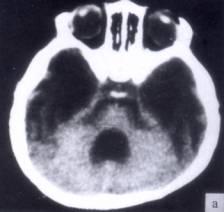

病历摘要:??患者女性,10岁。结核性脑膜炎愈后8月,头痛伴恶心呕吐1周,并渐加重。体检:神清,精神差,反应迟钝,双眼底视神经乳头水肿,双眼外展差,余未见...

问题 病历摘要:??患者女性,10岁。结核性脑膜炎愈后8月,头痛伴恶心呕吐1周,并渐加重。体检:神清,精神差,反应迟钝,双眼底视神经乳头水肿,双眼外展差,余未见明显异常。 下列关于脑脊液的叙述哪些是正确的?